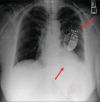

Twiddler's syndrome refers to malfunction of pacemaker or implantable cardioverter-defibrillator (ICD) resulting from deliberate or unintentional twisting of pulse generator in device pocket, resulting in lead dislodgment. We report a case of a 65-year-old woman with multiple ICD shocks and antitachycardia pacing events on device interrogation, while she was unaware of the ICD discharges. Twiddler's syndrome is rare and mostly occurs in obese or elderly because of loose subcutaneous tissue allowing pulse generator to rotate in its pocket. It can be prevented by patient education against hand manipulating the generator. Smaller device pocket or suturing generator to fascia can also prevent future episodes.